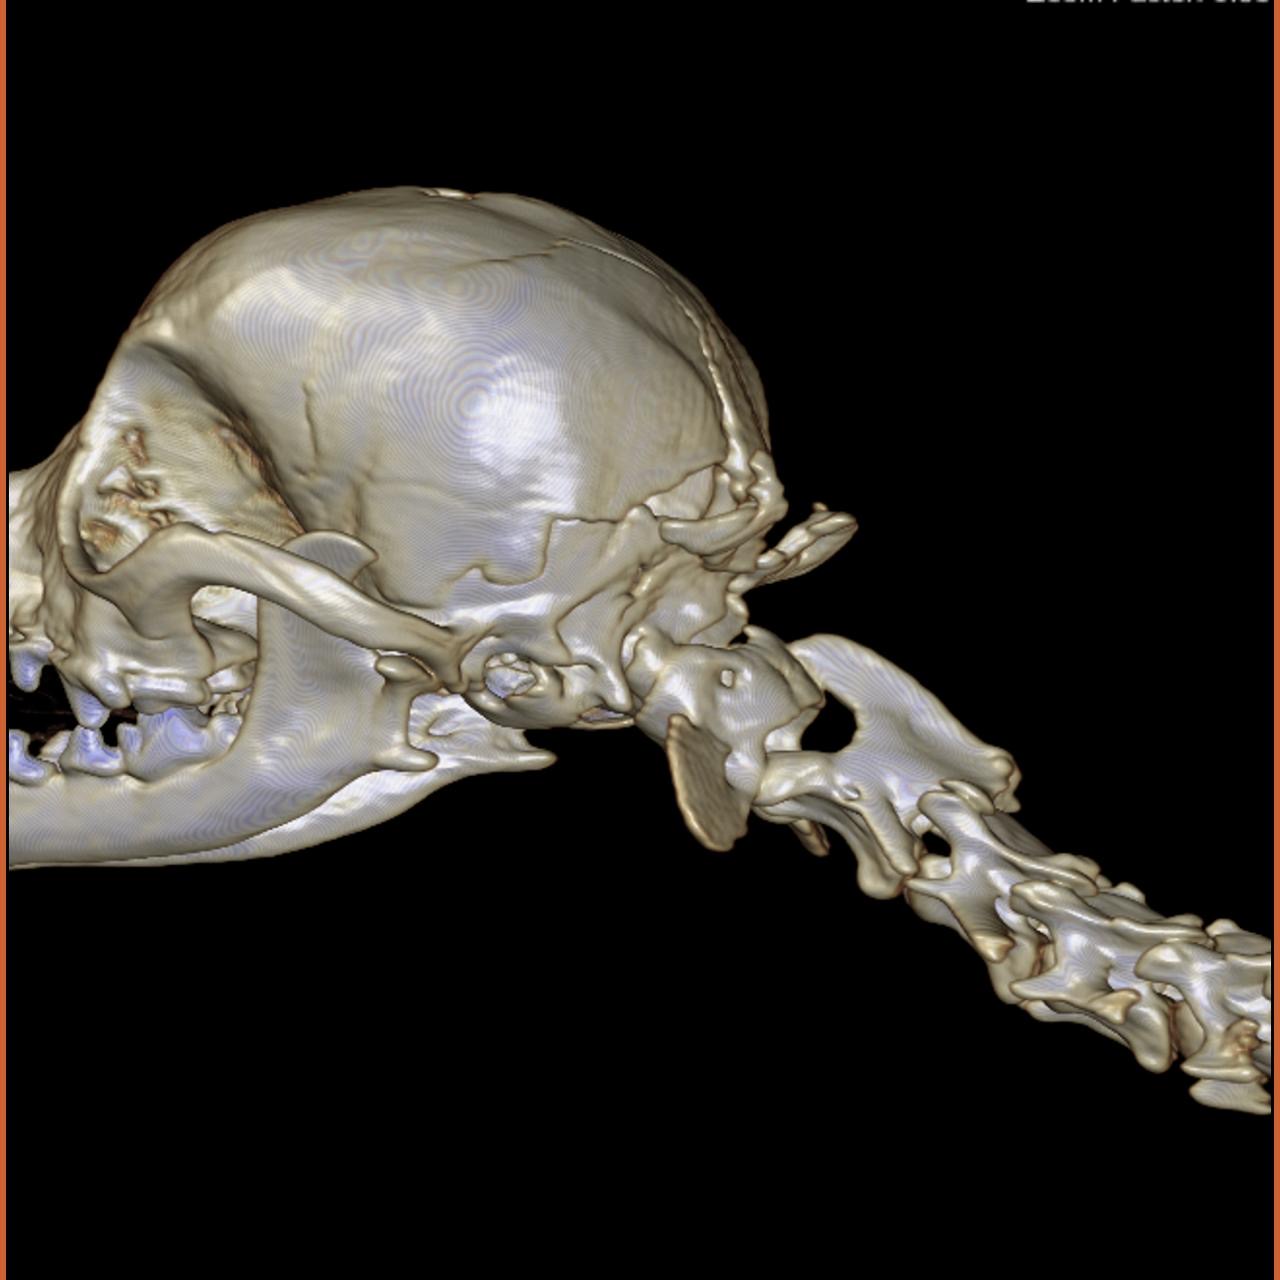

Dentro de CENEV contamos con especialistas dedicados al área de imagenología, dedicados al diagnóstico por pruebas como ultrasonido abdominal, radiología de tórax y abdomen, entre otras.

Nuestros equipos y personal especializado permiten estudios rápidos y de alta calidad para apoyar el diagnóstico clínico.